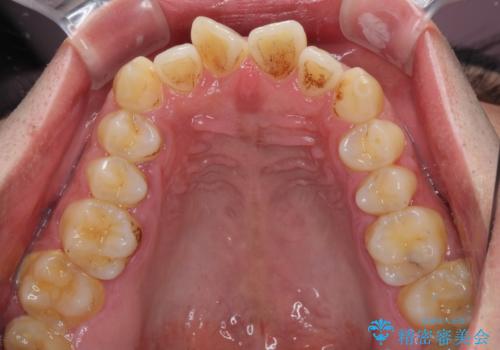

- 前歯が捻れており出っ歯であることを気にして来院された患者様です。

虫歯がほとんどなく、前歯以外にも歯列に問題があったため、歯列矯正を第一選択として強く勧めました。

しかし、時間をかけることは避けたいという強い要望があったため、セラミッククラウンによる補綴治療を行うこととしました。

補綴治療に先立ち、歯の形態を修正する必要があったため、残念ではありますが根管治療を行うこととしました。